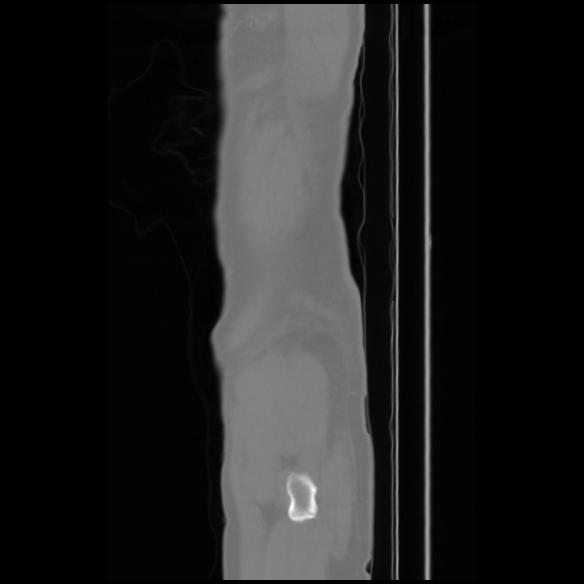

7 CUERPO,CE,Sagittal,3.000,CUERPO,Sagittal,